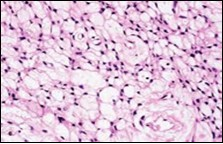

Figure 4.Soft tissue perineurioma composed of whorls and perivascular aggregates of neural cells with bipolar cytoplasmic processes, wavy, slender nuclei and commingled collagen fibres 13.

Soft tissue perineurioma composed of whorls and perivascular aggregates of neural cells with bipolar cytoplasmic processes, wavy, slender nuclei and commingled collagen fibres 13.